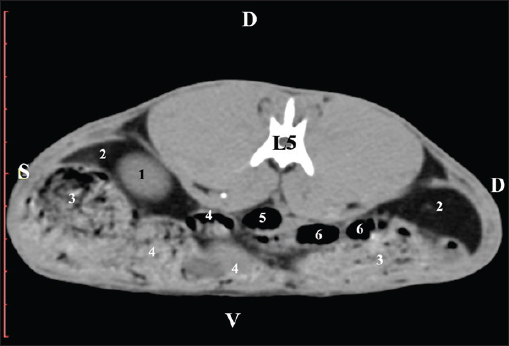

Fig. 11. Pre-contrast computed tomography (CT) anatomical scan of the regio-abdominis media at the caudal L4 edge level. (1) Ren sinister; (2) pelvis renalis; (3) ureter; (4) adipose collections; (5) cecum; (6) colon ascendens; (7) colon transversum; (8) colon descendens; (9) mesenterium; (white arrows) recessus renalis; (*) crista renalis. The L5 scan revealed the caudal end of the left kidney. It was adjacent to some small intestinal segments, including the duodenal pars ascendens, ileum, cecum, and colon ascendens (Figs. 12 and 13).

Fig. 12. Pre-contrast computed tomography (CT) anatomical scan of the regio-abdominis media at the cranial L5 edge level. (1) Ren sinister; (2) adipose collections; (3) cecum; (4) colon ascendens; (5) jejunum; (6) pars ascendens of the duodenum; (7) colon transversum; (8) colon descendens.

Fig. 13. Pre-contrast computed tomography (CT) anatomical scan of the regio-abdominis media at the caudal L5 edge level. (1) Ren sinister; (2) adipose collections; (3) cecum; (4) colon ascendens; (5) colon transversum; (6) colon descendens. Post-contrast CT imagingCT anatomical study at the Th13 level was used to define the right kidney zones. The medulla renalis was found as a hyperattenuated soft tissue with peripheral linear and wavy margins that reached the relatively hypoattenuated renal cortex. The most peripheral structure was the capsula adiposa, characterized by hyperattenuated soft tissue and uniform relief. The hyperattenuated aorta abdominalis, v. cava caudalis, and a. renalis appeared medially to the right kidney (Fig. 14).